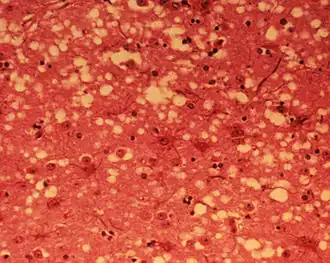

Los síntomas que se observan están motivados por la acumulación del prion en las células neuronales originando la muerte celular. Un análisis microscópico revela lesiones como vacuolas que dan al tejido nervioso un aspecto de esponja.